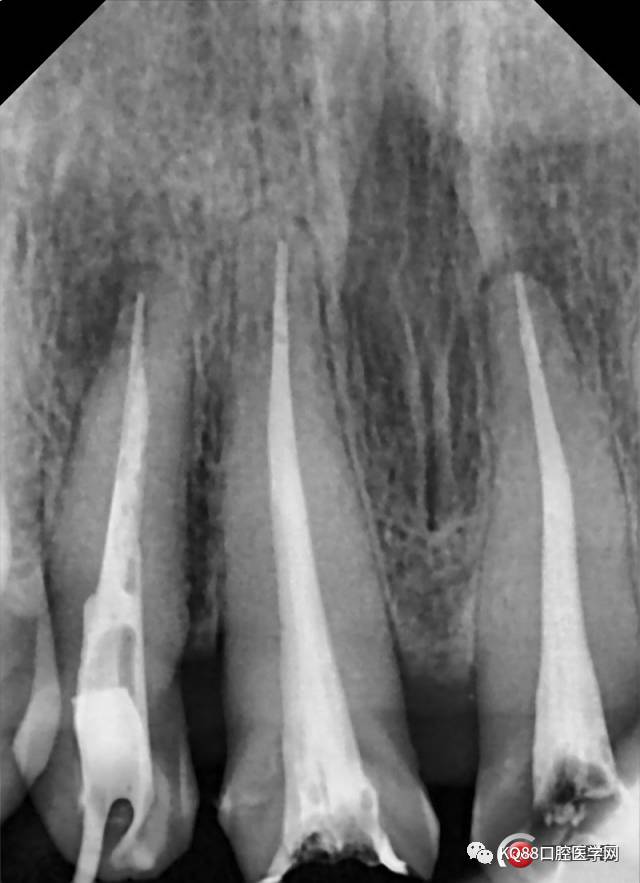

可见A2根尖偏远中有暗影,12 11 21根管治疗均不完善,然后开始拆冠,牙周治疗,根管治疗